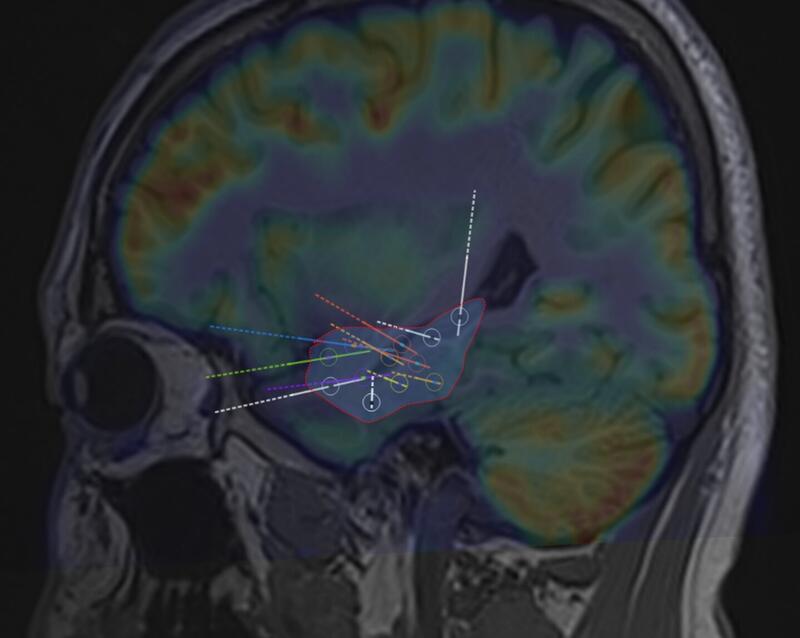

据杨治权教授介绍,这种微创毁损不同于目前大多数医院采用的常规毁损,这种毁损的特点是切除性或离断性毁损,即采用单根电极和多根电极的立体交叉毁损,根据致痫灶的形态,设计三维立体的拓扑毁损范围,从而达到切除病灶的效果,这是方法上根本改进。

应用单根电极和多根电极进行立体交叉拓扑毁损,从而达到切除性毁损的目的

根据致痫灶的不同形态,设计立体三维拓扑毁损方案,从而达到不开颅即可全部毁损病灶的目的!